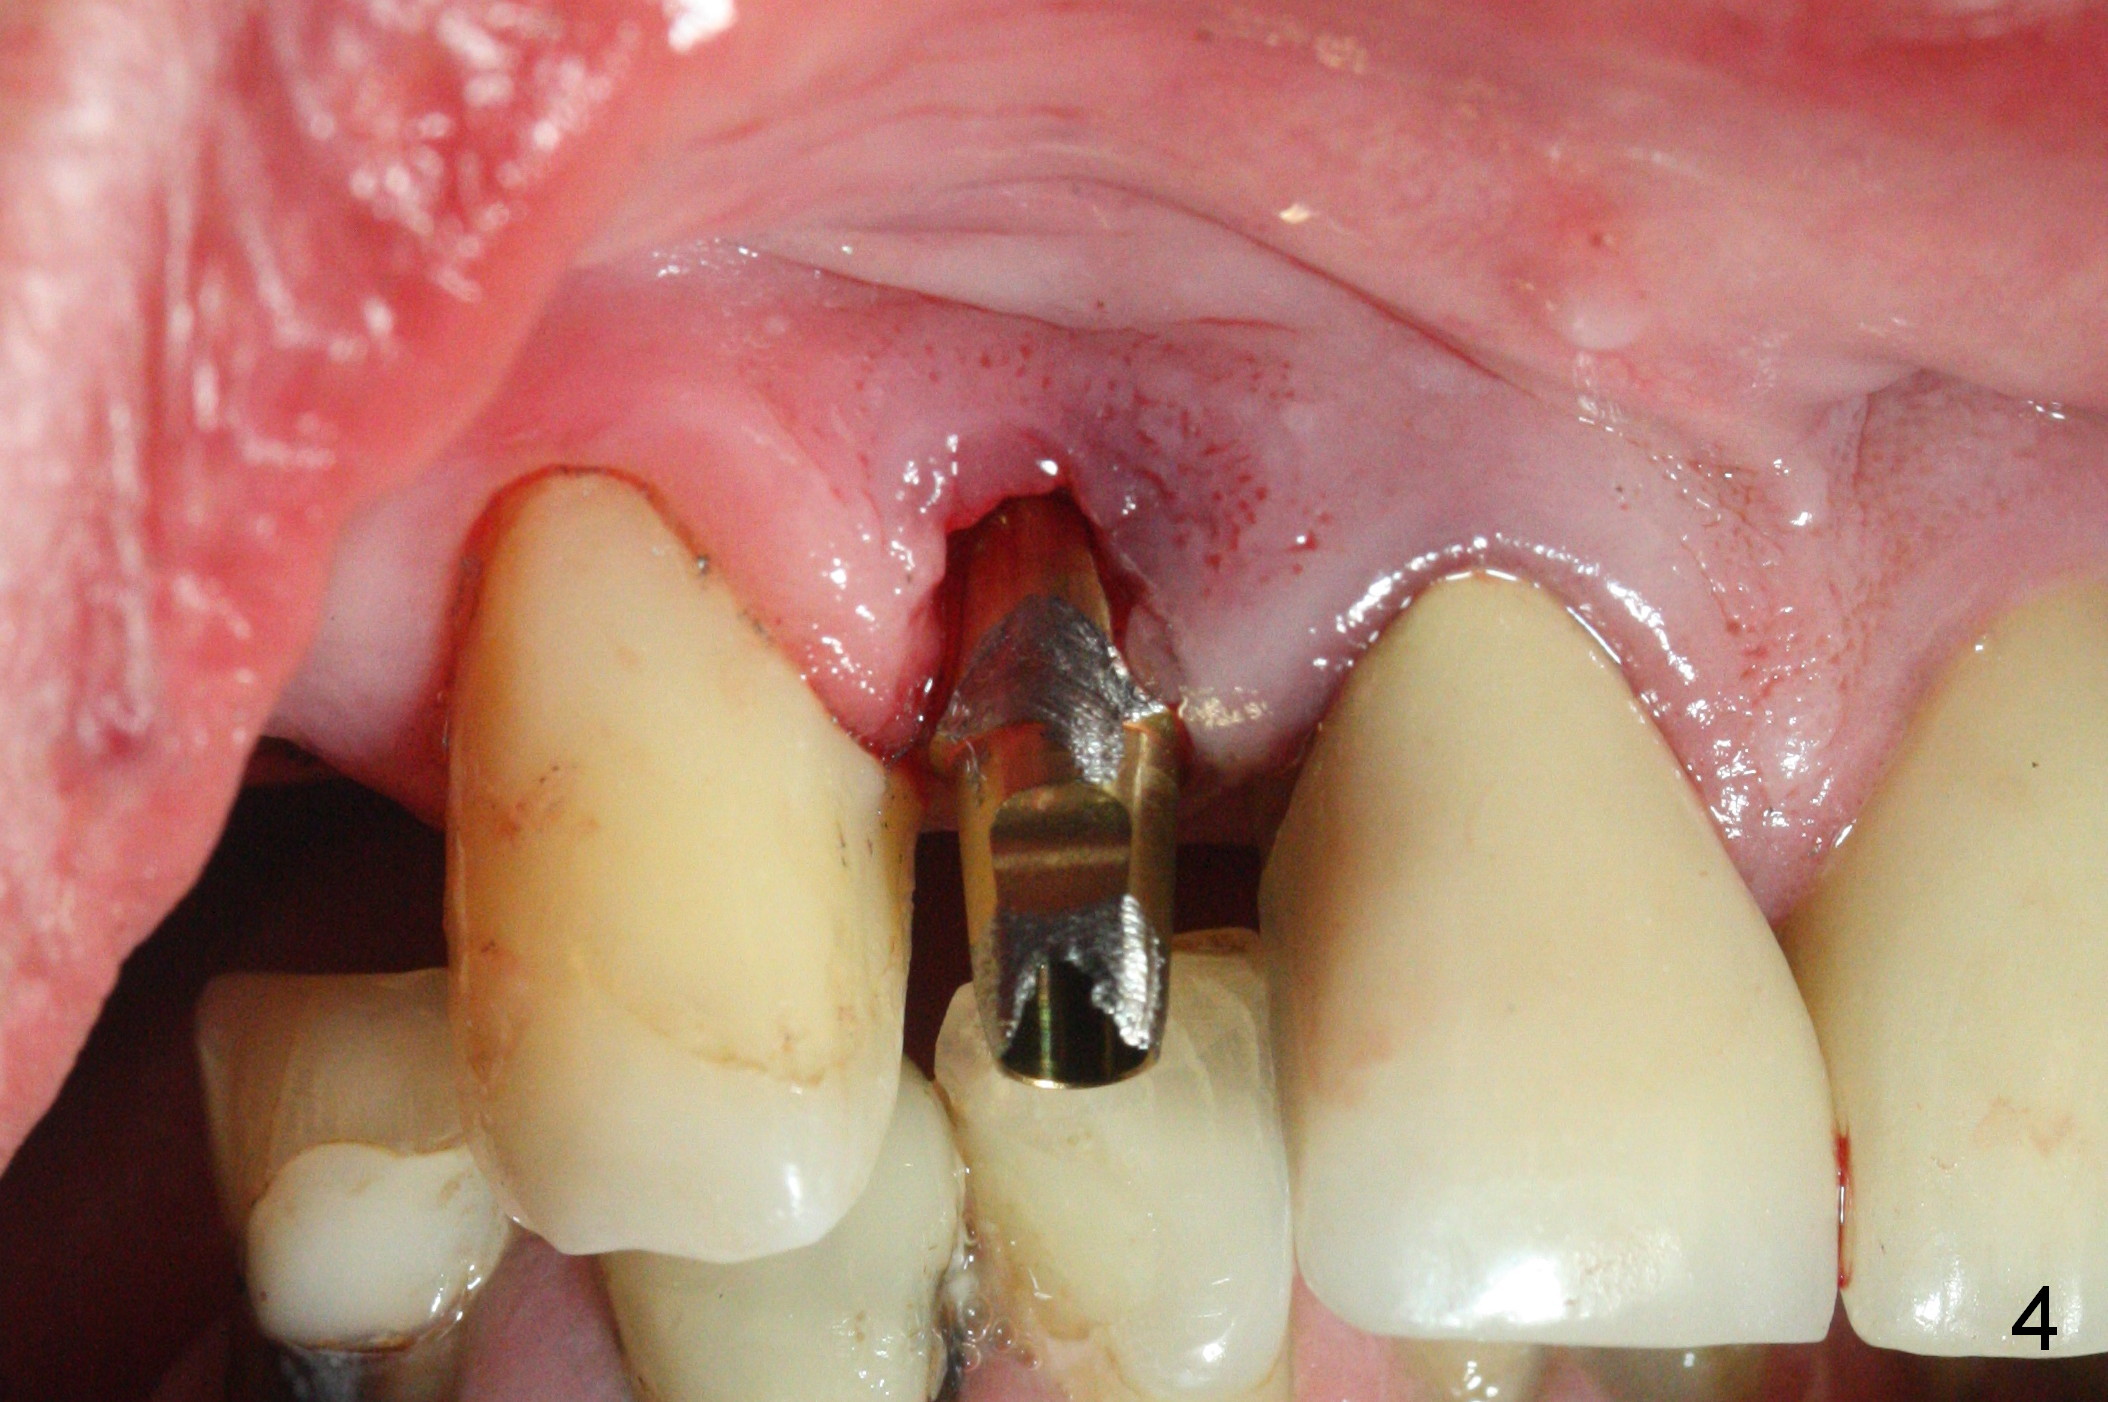

The residual root at #7 is fairly well exposed with buccal gingival recession (Fig.1). The implant placement is flapless (Fig.2-7). What is not shown is that the 3.8x13 mm implant is buccally subcrestally placed (Fig.3). After 1st round of bone graft buccal to the implant, a 4.5x5(5) mm abutment is immediately placed and prepared (Fig.4,5). An immediate provisional is placed after 2nd round of bone graft subgingivally buccally (Fig.6,7). Note the bulging gingiva (*), as compared to that in Fig.4,5. The long implant is chosen because of anterior deep bite (Fig.4) and lack of posterior support (Fig.7).